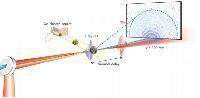

Мобильный рентгенаппарат + оцифровщик. Получение рентгеновского изображения на экране ноутбука. Вариант за 1,4 миллиона рублей под ключ.